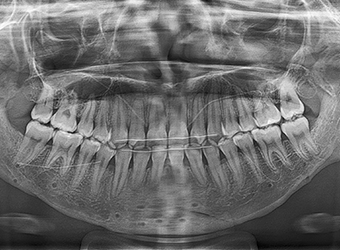

얼굴 턱뼈 수술에서는 절단 후 분리된 뼈를

새로운 위치에 고정하기 위해 고정핀을 사용합니다.

이 핀은 뼈가 충분히 회복된 후, 핀제거 수술을 통해 제거할 수 있습니다.

• X-ray, CT 등

방사선 촬영에서 핀이

보이고 싶지 않은 경우